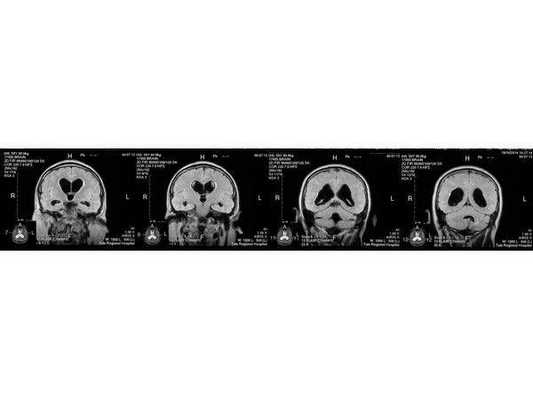

- МРТ в динамике показывает постепенное сужение желудочковой системы на 2 мм. Для сравнения представлены снимки МРТ от 14.05.2013 и от 16.10.2014.